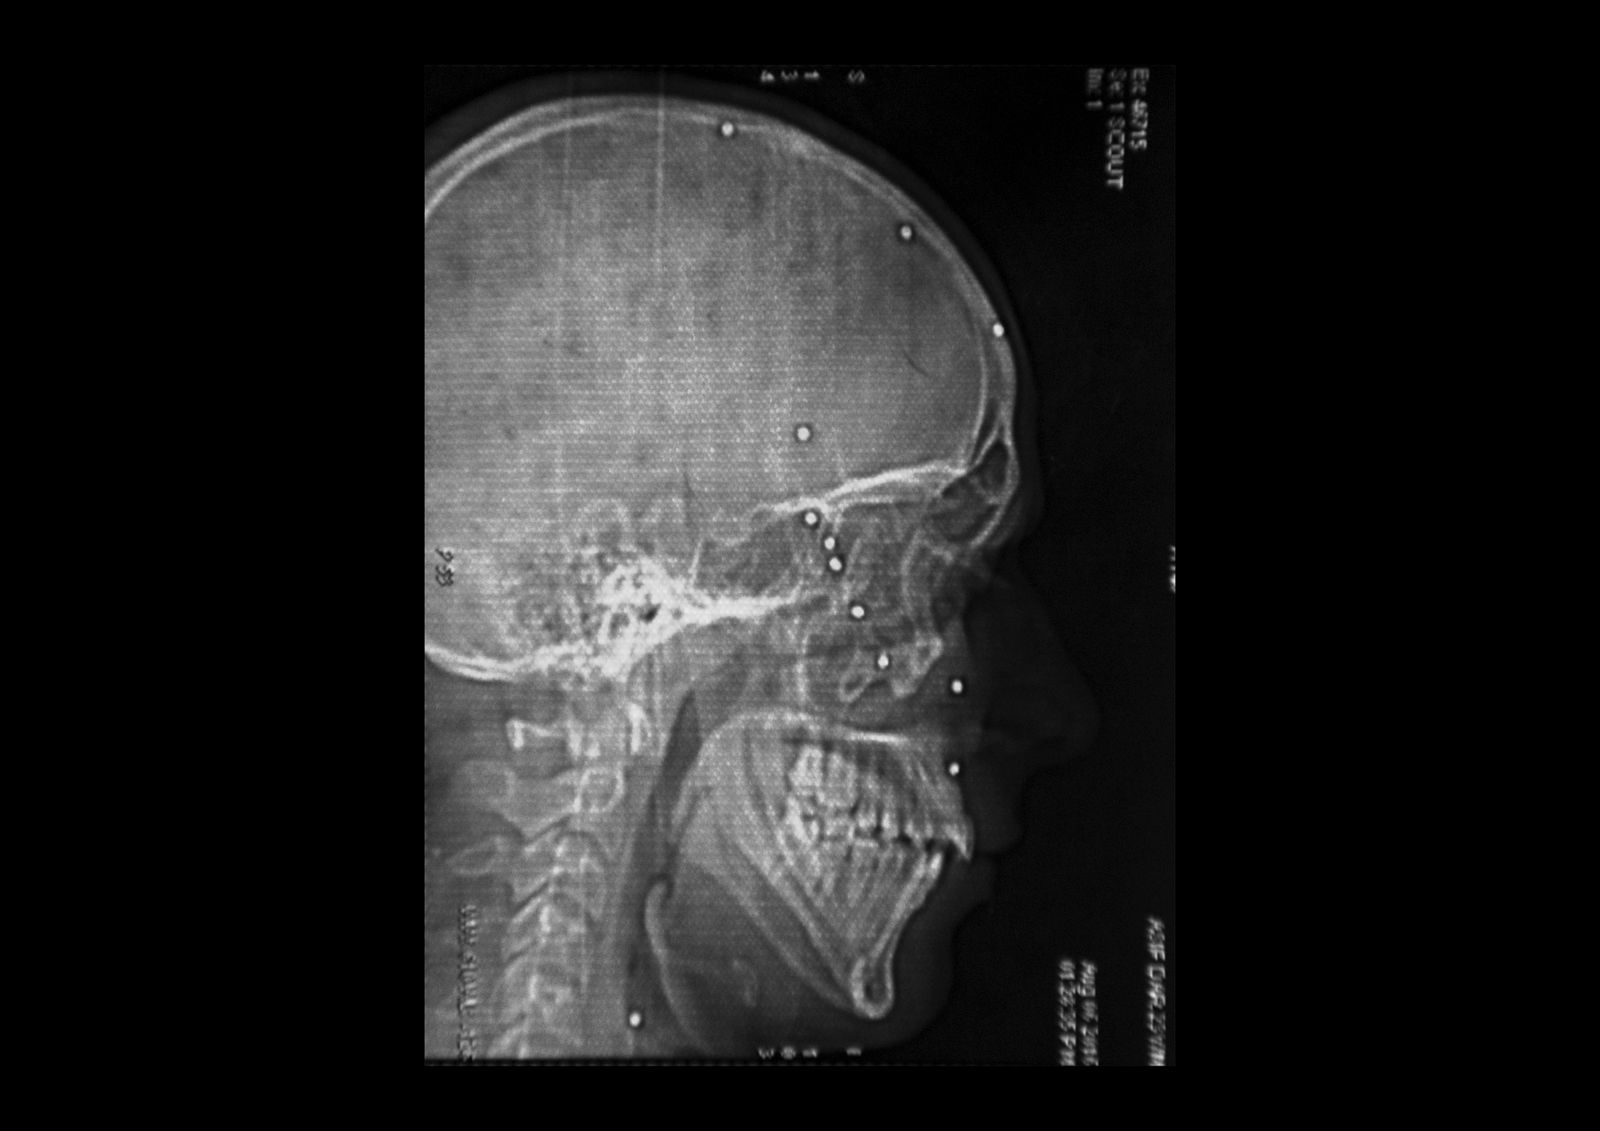

Danish Rajab Jhat, 24 years old, Srinagar. “It was evening time and the police was chasing the stone thrower in my neighborhood. I was just sitting on the side of the road and they shot me. I don't remember anything about that moment, i woke up in the hospital. The left eye was entirely damaged so the doctors replace it with an arti cial eyeball”. A shell entered through the left eye and the pellets dispersed all over the the head damaging also the righ eye. Danish has still 90 pellets inside hi body and from the right eye he can barely see shadows.

i